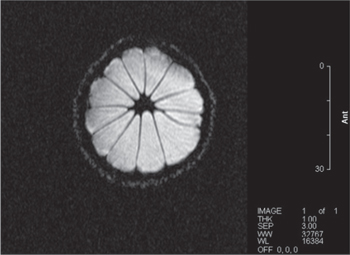

With the magnet operating stably, and with a good level of shim achieved, we performed some MRI images on fruit. We were able to achieve both spin-echo [19] as can be seen in figures 22 and 23 and gradient-echo [19] images as can be seen in figures 24 and 25.

Standard image High-resolution imageFigure 23. Spin-echo image of kiwi fruit. Axial image, 80 × 80 mm FOV. TR = 3000 ms, TE = 75 ms. 2 mm slice.

Download figure: